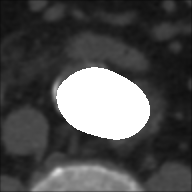

From ROIs are created the binary masks for each slice of the sequences both for basal and with CM.

Masks are produced with elliptical selection to include the entire vessel, and the pixels within the selected ellipse assumes as intensity value (white), while all the remaining ones takes (black).

At this point, the dataset is ready for the processing in the portal ImageLab. The latter, takes as input the basal ROI and its corresponding CM one, together with their respective binary masks. These, are used by the algorithm to create the image (see Fig. 2), and consequently to detect the vessel. As depicted in Fig. 4, in output the extracted image is provided, along with a colored map where green highlights pixels correctly classified by the algorithm, red indicates misclassified ones, and white indicates the areas the algorithm should have identified but did not. Adjacent to this, similarity indices described before are presented, computed by considering the CM image as the target, which is provided as input for this purpose. We have processed in the portal each slice of our dataset.